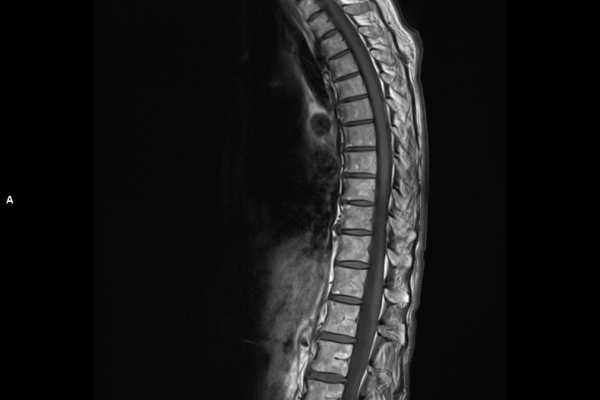

Detailbild MRT

Wir verbinden modernste Medizin mit einer Atmosphäre, in der Sie sich sicher und gut aufgehoben fühlen. Klare Abläufe, Ruhe und Zeit für Sie stehen im Mittelpunkt jeder Untersuchung. CT- und MRT-Bilder ohne Wartezeit. Mit Photon-Counting-CT und 3-Tesla-MRT setzen wir auf in Kärnten einzigartige Technologien für außergewöhnlich detailreiche Bilder und besonders präzise Diagnosen. Die schonenden Verfahren eignen sich auch für Kinder und Jugendliche. Kurze Messzeiten, große offene Geräte und ein ruhiges Umfeld sorgen für eine angenehme Untersuchung und ein gutes Gefühl von Anfang bis Ende.

Die MRT (Magnetresonanztomographie) arbeitet mit Magnetfeldern und Radiowellen und eignet sich besonders für Untersuchungen der Weichteile wie Gehirn, Muskeln oder Gelenke. Die CT (Computertomographie) nutzt Röntgenstrahlen und liefert schnelle, hochauflösende Bilder, insbesondere für Knochen, Lunge oder innere Organe. Die Wahl der jeweiligen Untersuchung richtet sich an das individuelle Krankheitsbild und wird bei der Überweisung festgelegt.